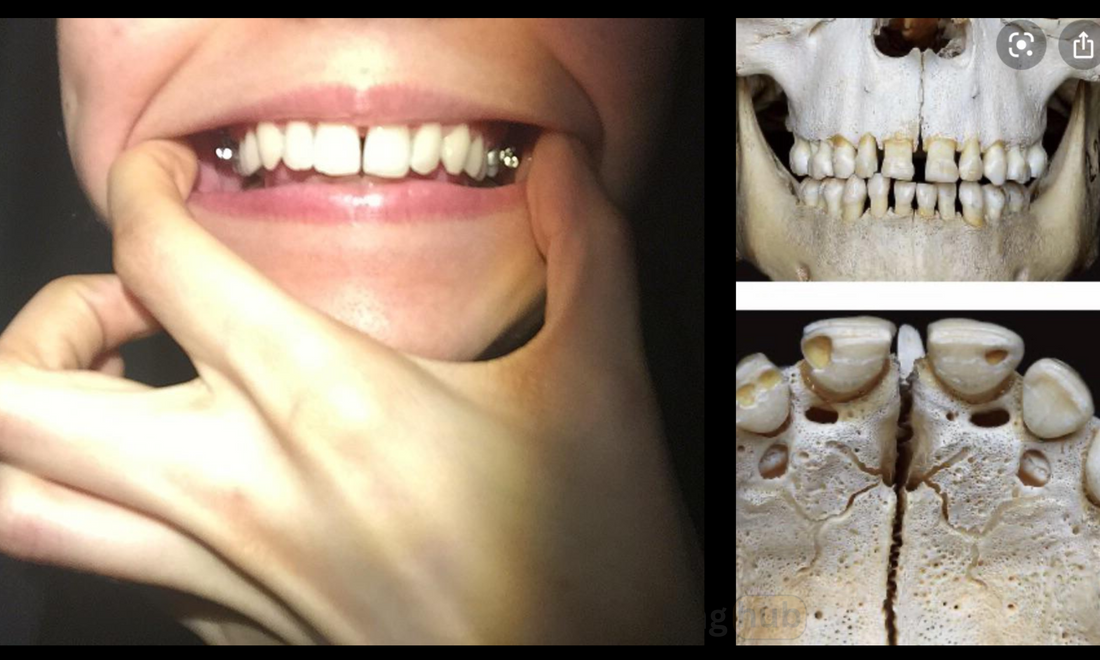

Images showing the midpalatal suture split.

The midpalatal suture is the joint located in the roof of the mouth that can potentially widen the upper jaw when split. There’s growing speculation about whether mewing—the practice of tongue posture against the roof of the mouth—can influence this suture.

Two images of mewers who have achieved a split of the midpalatal suture with mewing.

Two Cases of Mewing causing a suture split